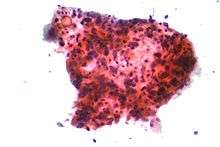

_by_core_needle_biopsy.jpg)

In small-cell lung carcinoma (SCLC), the cells contain dense neurosecretory granules (vesicles containing neuroendocrine hormones), which give this tumor an endocrine/paraneoplastic syndrome association.[68] Most cases arise in the larger airways (primary and secondary bronchi).[13] Sixty to seventy percent have extensive disease (which cannot be targeted within a single radiation therapy field) at presentation.[6]